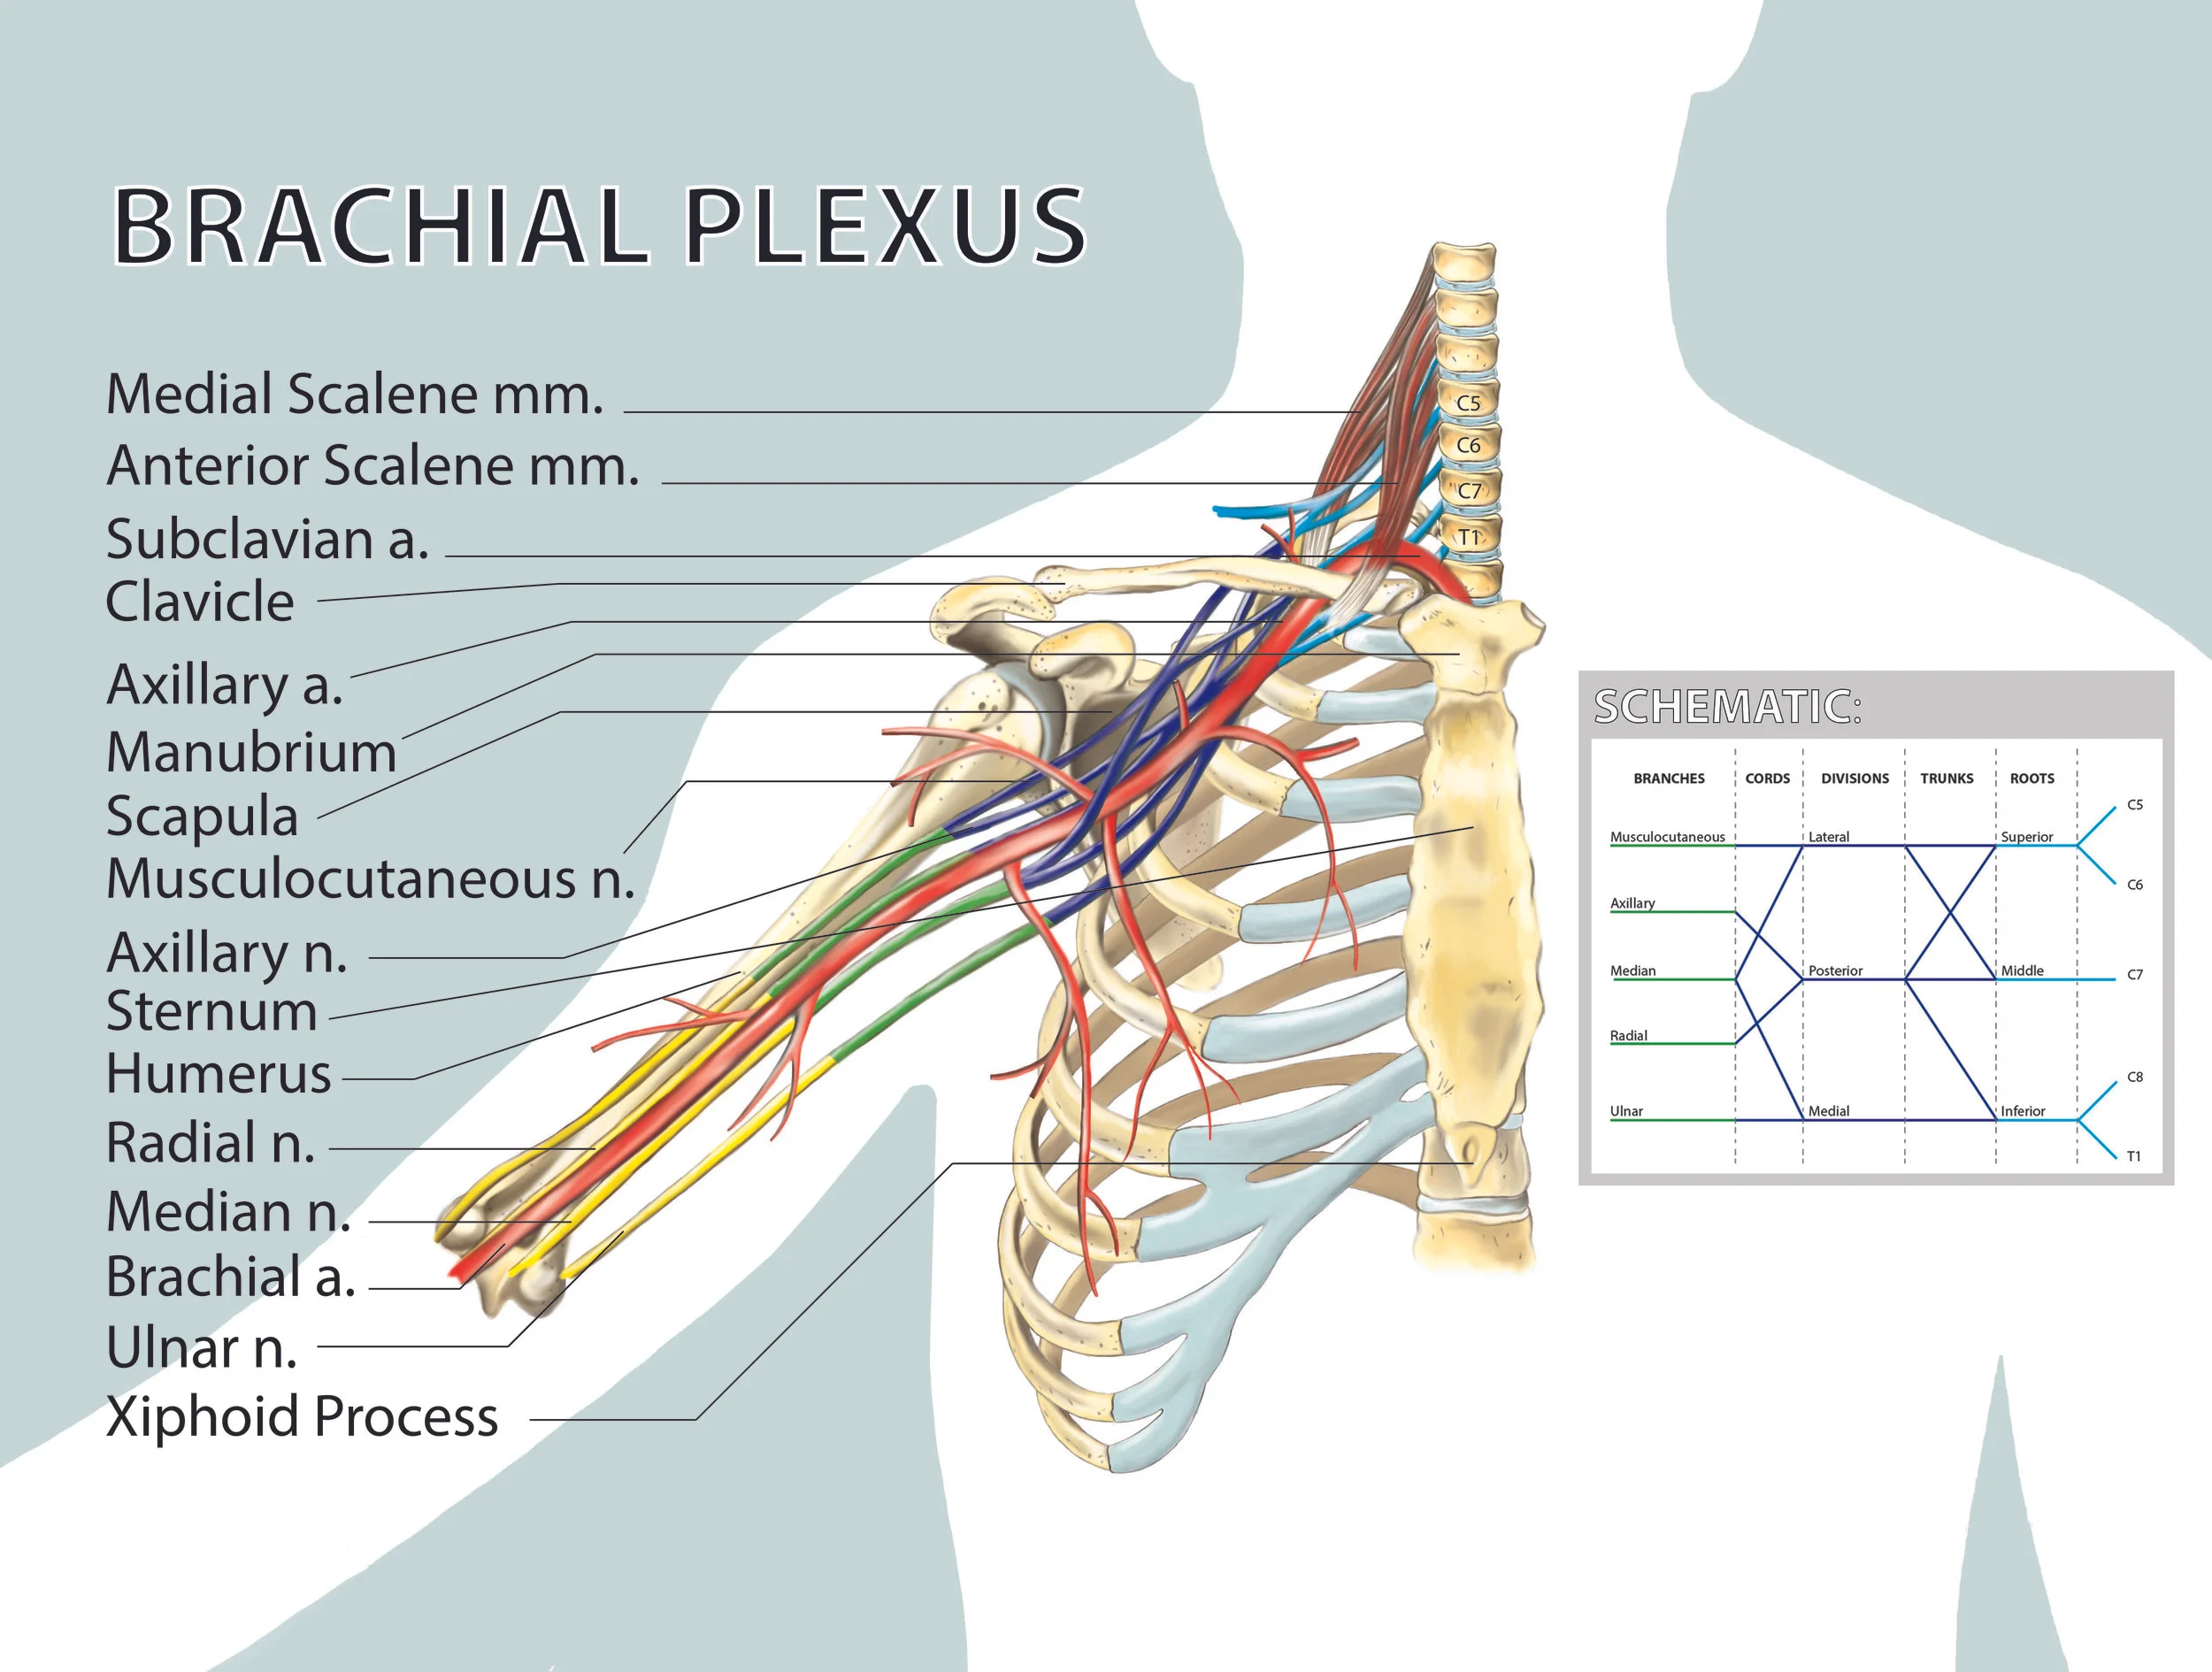

Biomedical art is a form of biological illustration that helps record and disseminate medical, anatomical, and related knowledge. It translates complex technical medical information into visual artwork to support research, patient care and education, public relations, and marketing objectives.